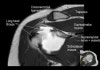

Long head 바깥의 고신호는 Biceps groove의 Normal fluid

Acromion의 하면에 부착하는 저신호 : Deltoid tendon or Corocoacromial ligament일수도 있음

Enthesophyte로 오진가능하나 정상 부착부 소견